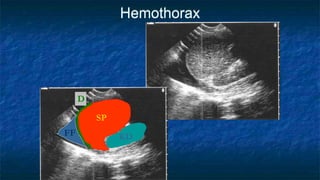

Extended FAST (E-FAST)

RUQ, LUQ views:

 Check above diaphragm for hemothorax

 CXR = US in detection of hemothorax

Ma and Mateer. Ann Emerg Med, 1997

 50-175cc vs. 20cc or less

 US does not replace CXR

Hemothorax

KD

SP

FF

D

Pleural Fluid